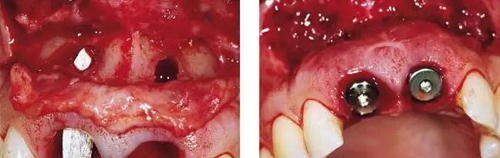

圖6、從磨牙后區(qū)用環(huán)形鉆獲取自體骨,并將其放置在種植體的表面。Geistlich Bio-Oss®骨顆?;旌涎悍胖迷谧泽w骨的外側(cè),防止自體骨的早期吸收。植骨可以穩(wěn)定軟組織外形。

圖7、植骨區(qū)外覆蓋Geistlich Bio-Gide®雙層膠原膜,使得植骨區(qū)更為穩(wěn)定。

圖8、從上腭獲取結(jié)締組織縫合在黏骨膜瓣上,進(jìn)行軟組織增量。為了使得黏骨膜瓣充分減張情況下關(guān)閉,應(yīng)該使用瓣的分層技術(shù)。使用6-0或者5-0的可吸收線縫合關(guān)閉傷口。4個(gè)月后進(jìn)行二期手術(shù)時(shí)通過(guò)分裂瓣技術(shù)將色素沉著的牙齦向冠方復(fù)位以恢復(fù)其原來(lái)的自然外形(在此沒(méi)有展示)。

圖8、植入2顆Camlog平行壁螺紋種植體,扭矩達(dá)35Ncm。安放兩個(gè)粗直徑的愈合帽,防止軟組織退縮和凹陷。

圖9、頰側(cè)骨壁用自體骨覆蓋,Geistlich Bio-Oss®覆蓋在自體骨的外側(cè),Geistlich Bio-Oss®同樣也要放置在基臺(tái)與牙齦之間,以支撐牙齦的外形。